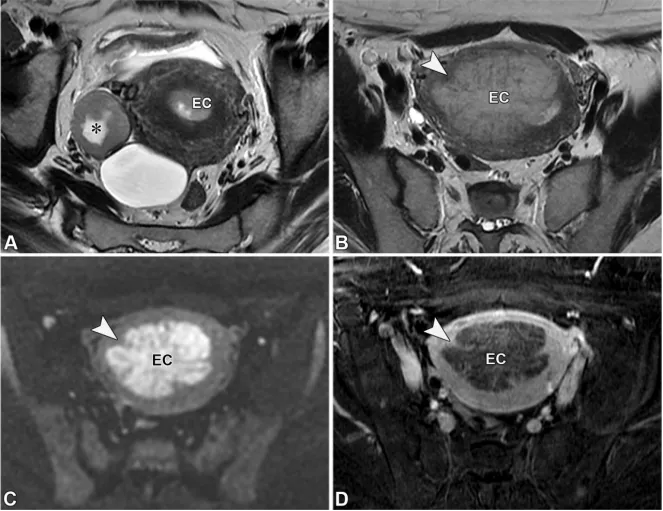

对于30岁以下、单侧卵巢实性病变且乳酸脱氢酶升高的女性,最可能的诊断是无性细胞瘤(36,62)。无性细胞瘤是一种恶性生殖细胞肿瘤,为睾丸精原细胞瘤的卵巢对应肿瘤,表现为单侧非低信号T2/非低信号DWI实性病变,由T2低信号、强化明显的纤维血管间隔分隔成小叶(图28)(62)。相反,在30岁以下女性中,甲胎蛋白升高基本可诊断为卵黄囊瘤,而β-人绒毛膜促性腺激素升高基本可诊断为绒毛膜癌(36,62)。

图28. 一位20岁女性患者的左侧卵巢无性细胞瘤,其乳酸脱氢酶(LDH)水平升高。轴位T2加权像(A)、高b值扩散加权像(B)、表观扩散系数(ADC)图(C)及对比增强脂肪抑制T1加权像(D)显示,卵巢存在一个T2信号中等的实性病灶,伴有弥散受限(B图呈高信号,C图呈低信号)且有强化。该病灶被纤维血管间隔分隔成小叶,这些间隔在T2加权像上呈特征性的中低信号(A图箭头),在对比增强像上呈明显强化(D图箭头)。